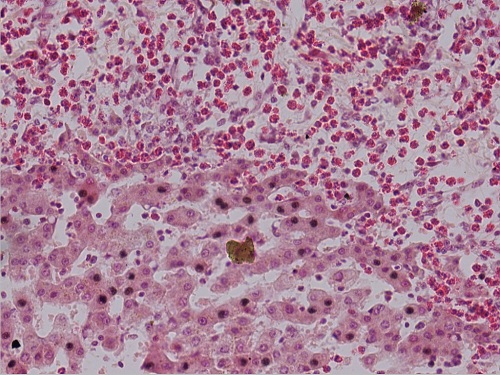

蛔虫性肝硬变1(肝小叶间有大量嗜酸性粒细胞)10X40

蛔虫性肝硬变3(肝小叶间有大量嗜酸性粒细胞,有蛔虫虫体)10X40